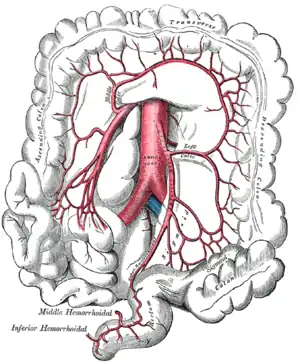

Blood supply comes from three arteries branching off the aorta: the coeliac artery, the superior mesenteric artery, and the inferior mesenteric artery.

Inferior Mesenteric Artery

Supplies blood to the colon. Again notice the system of arching anastemoses.